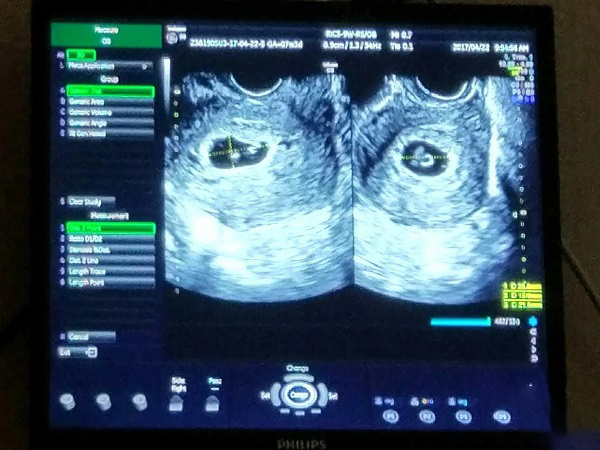

双绒双羊和单绒双羊其实就是怀双胞胎的两种情况。一般来说双胞胎分为双绒双羊、单绒双羊、单绒单羊三种,前者是双卵双胞胎,后两者则是但单卵双胞胎。据统计,自然受孕怀上双胞胎的几率是非常低的只有1%,其中双卵也就是双绒双羊的占三分之二,单绒双羊和单绒单羊的占三分之一。虽然,双绒双羊和单绒双羊都表示女性已经怀上双胞胎,但其实这两者之间存在很大的差异,在受精卵个数、危险性等方面存在着区别。

1受精卵个数:双绒双羊是由两个受精卵发育而成,属于异卵双胞胎,而单绒双羊是由一个受精卵发育而成的,两个孩子以后的长相和性格都是比较相似;2胎盘数量:双绒双羊有两个羊膜囊和两个胎盘,而单绒双羊虽然也有两个羊膜囊,但是两个胚胎需要共用一个胎盘;3危险性:正是由于单绒双羊两个胚胎共用一个胎盘,所以两个胎儿相互影响,相互争取营养的情况就会时常发生,进而导致早产的风险性高,而双绒双羊因为两个胎儿不存在互相影响,所以不容易发生早产。

双绒双羊和单绒双羊都是双胞胎,但是也存在异卵和同卵的区别。一般来说,双绒双羊就是指女性的两个卵子同时受精发育而成的,属于异卵双胞胎,但是也有可能是同卵这是不确定的。单绒双羊是由一个卵子和一个精子受精而成的,两个胎儿共用一个胎盘,拥有100%的基因,所以两者的长相和性别都是非常相似的。